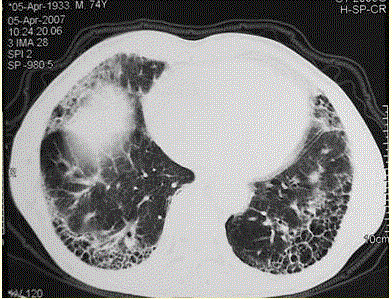

问题 患者男,73岁。进行性呼吸困难半年,加重2个月。否认吸烟史、粉尘接触史。查体:发绀,杵状指,双肺底闻爆裂音。血常规正常,ERS 16 mm/h。胸部CT 如图所示。 首选治疗方案中,最不适宜的是(提示 该患者支气管肺泡灌洗液显示:细胞总数3.6×10,嗜酸细胞28%,吞噬细胞35%,中性26%,淋巴11%。)

选项 A.大剂量甲强龙冲击治疗 B.口服泼尼松 C.富露施 D.抗生素 E.口服支气管扩张剂

答案 A